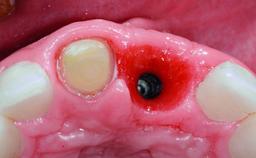

A healthy 37-year-old female patient was referred for a consultation on the replacement of missing tooth 21 with an implant-supported restoration. She stated that several years previously the tooth had been traumatically avulsed following a motor vehicle accident. The tooth was replaced with a three-unit fixed partial denture (FPD) immediately afterwards. Over time, she became disillusioned with the FPD and looked for a different option, including orthodontic therapy. She presented still in her orthodontic appliances, with the pontic sectioned free from the FPD but attached to the archwire. Her orthodontist felt that orthodontic treatment had been successfully completed, but nevertheless referred her before removing the appliances in case adjustments were necessary.

| Bone Augmentation | Horizontal|Simultaneous |

| Soft Tissue Grafting | Simultaneous |